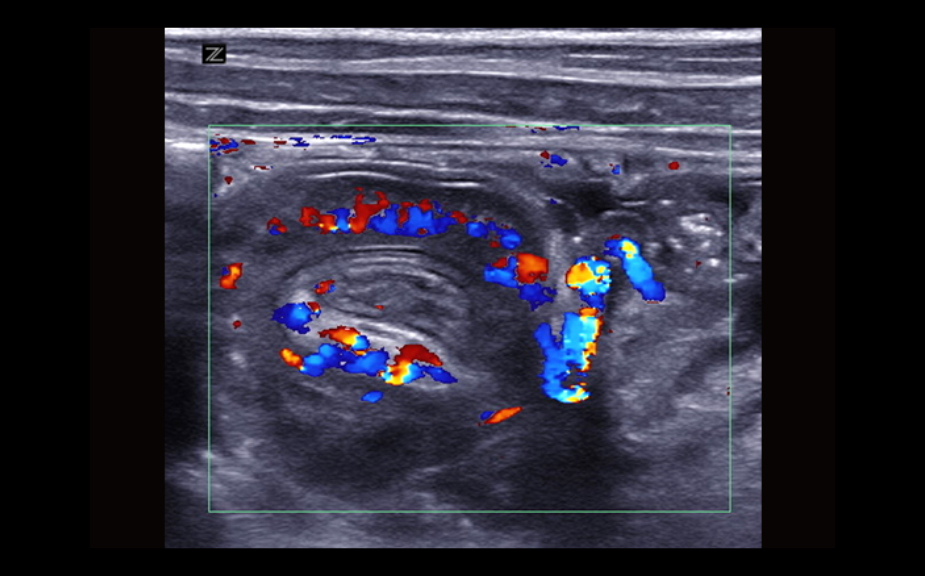

Equipped with patented, software based ZONE Sonography? Technology (ZST), the Z.One PRO provides optimally detailed B-mode and Doppler imaging for patients, regardless of body habitus, helping assure a reliable diagnosis.

Throughout a wide range of applications, the Z.One PRO is the ultrasound solution for your demanding clinical challenges.

- Unsurpassed image quality across all applications